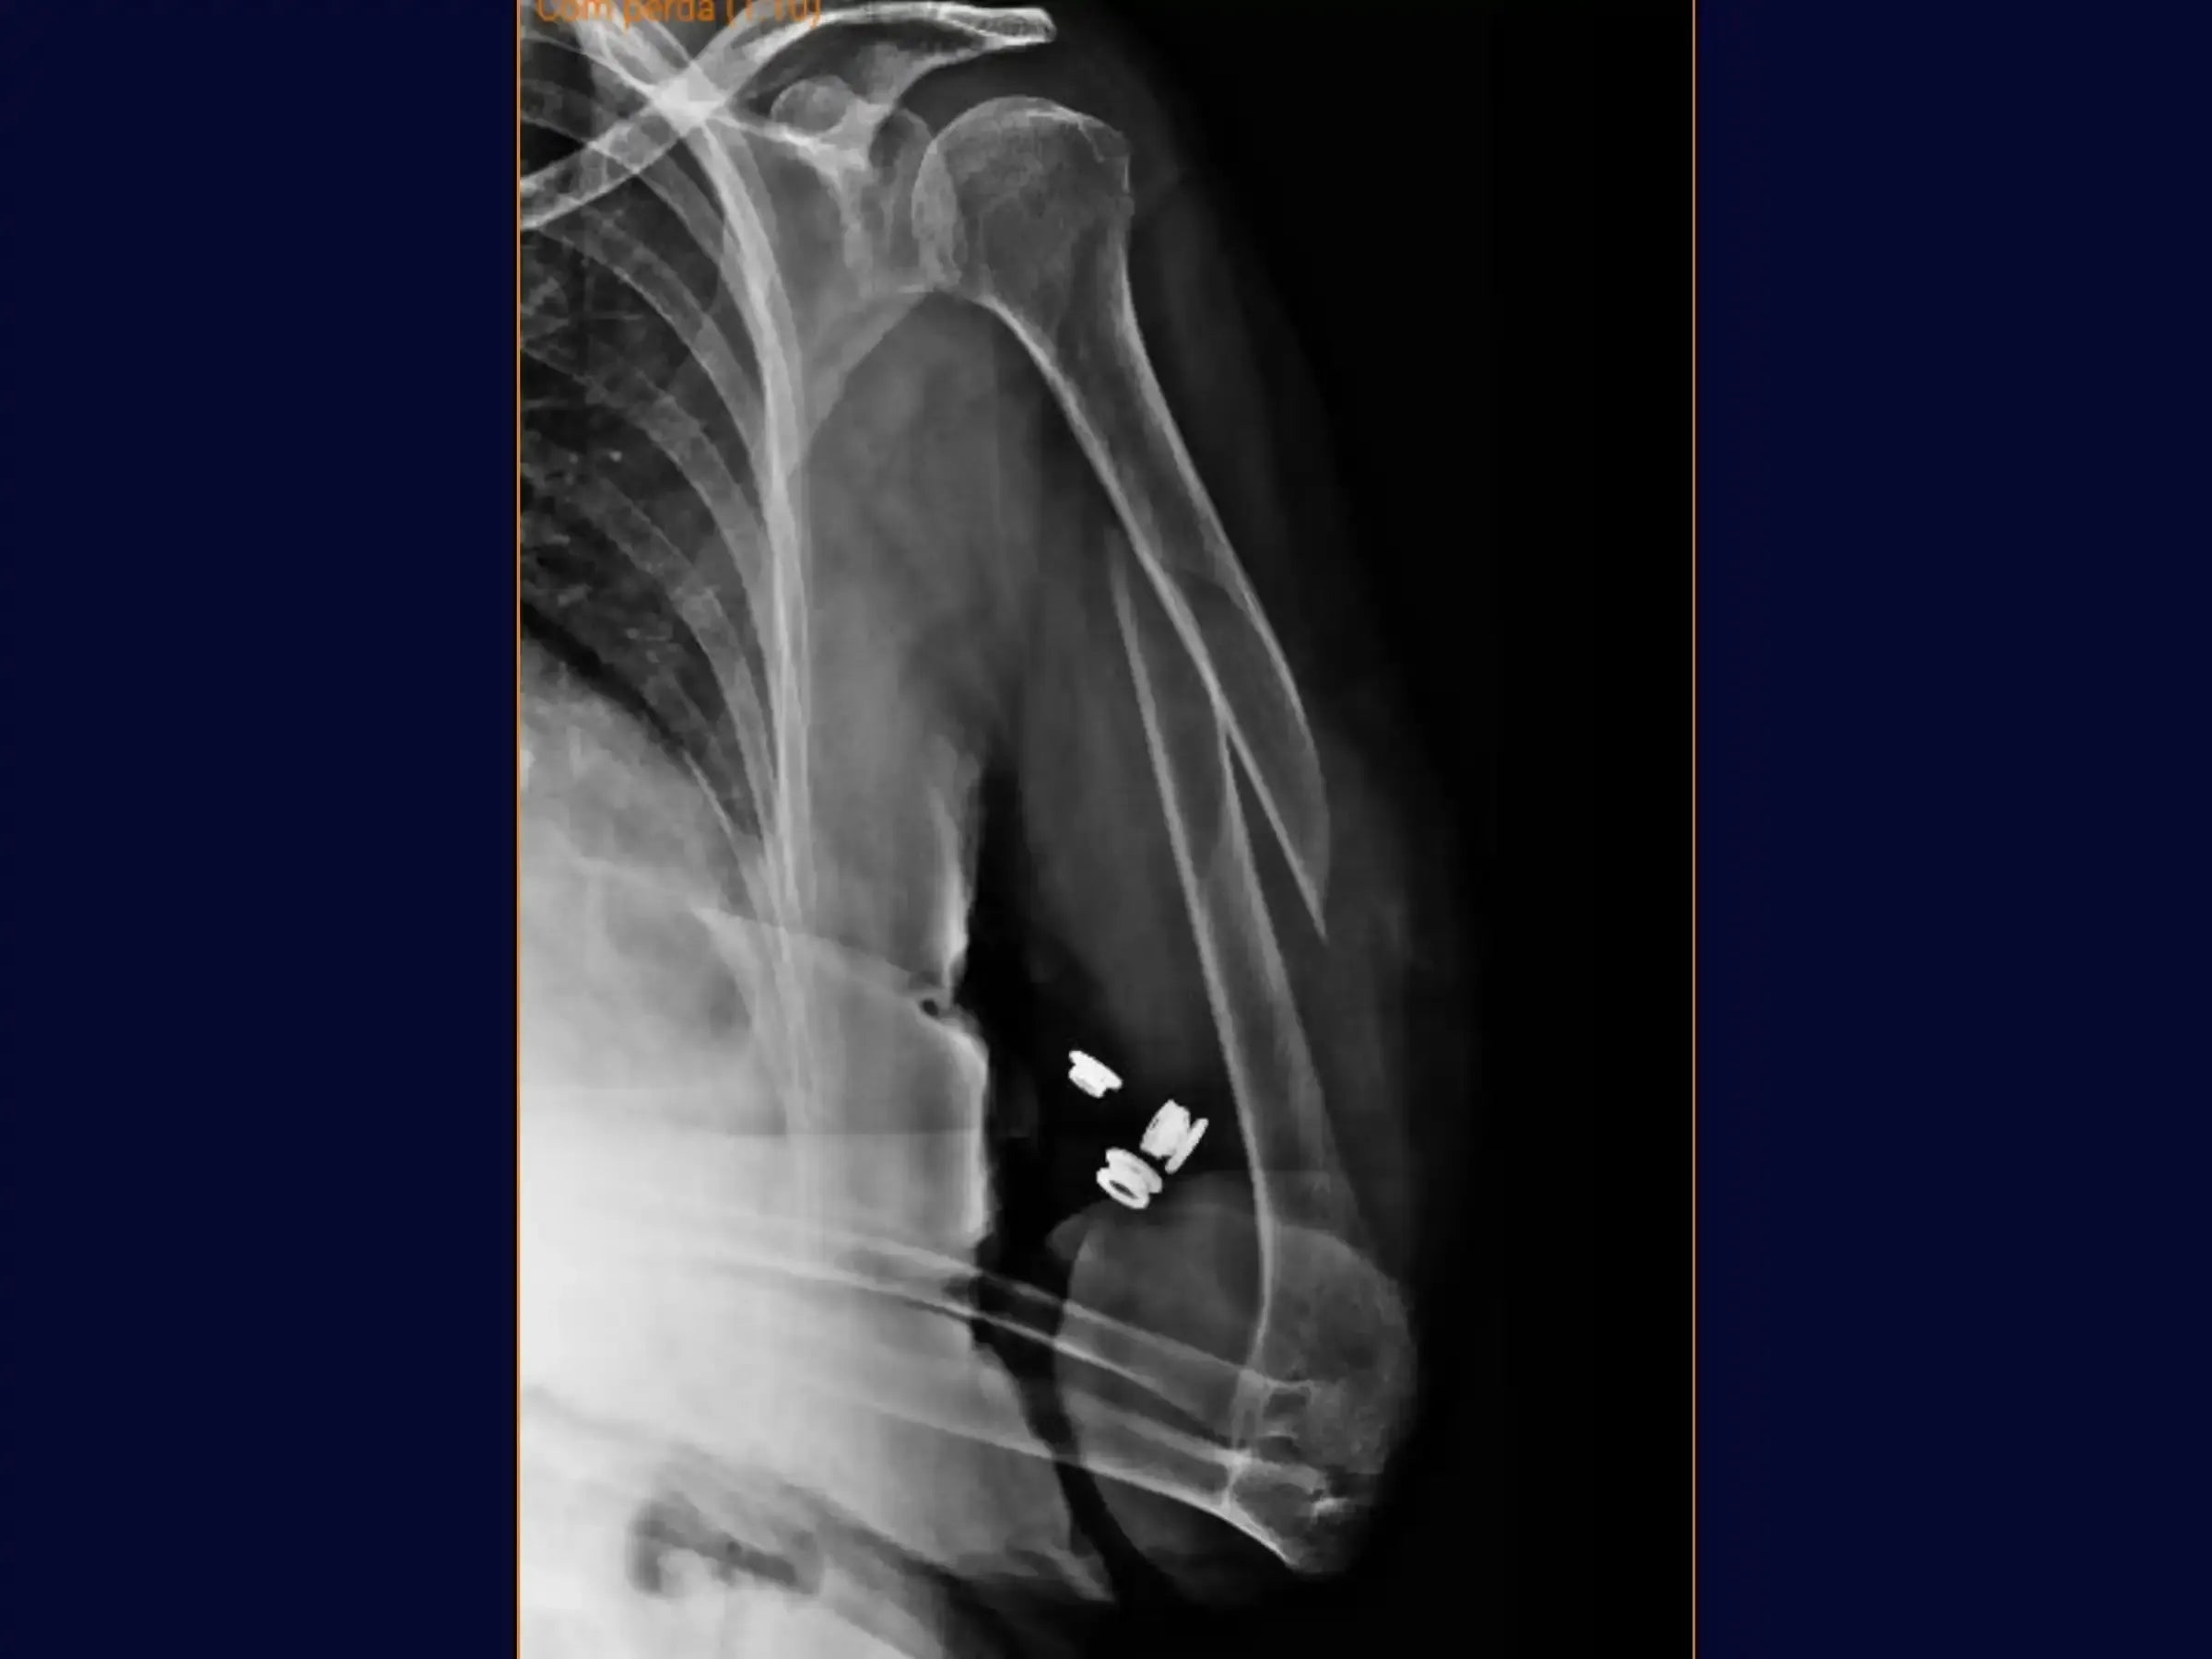

Diaphyseal Humerus Fracture - Treatment with Intramedullary Nail

Master the treatment of diaphyseal humeral fractures. This training offers a technical immersion in osteosynthesis with intramedullary nails, covering everything from planning to advanced reduction and locking maneuvers, to optimize your surgical outcomes.

- Treatment of diaphyseal humeral fractures.

- Intramedullary nail fixation technique.

- Initial Assessment and Marking: Learn to delineate the long axis of the humerus and identify the deformity and exact location of the fracture, using a dermographic pen for precise surgical planning.